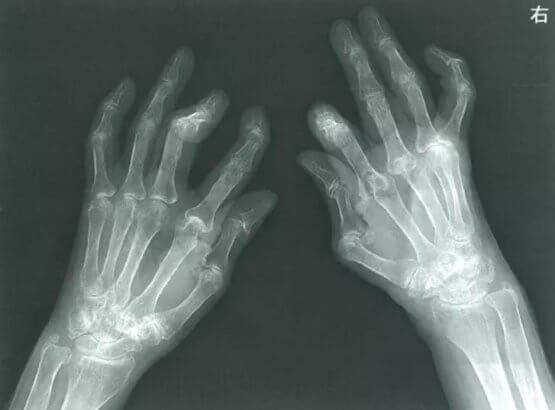

リウマチ患者に対する研究では、低気圧が接近すると関節の痛みや腫れが悪化することが明らかにされています。この研究は、天気痛や天気コリが迷信ではなく、実際に科学的根拠に基づいた現象であることを裏付けています。